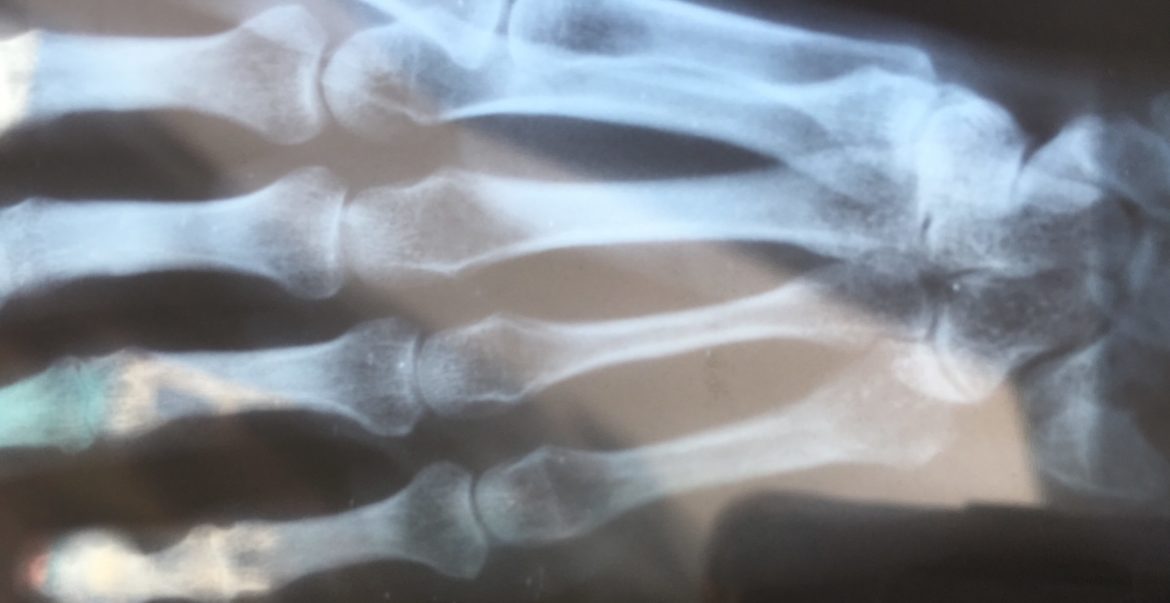

The orthopedist was pleasant and knowledgeable and had spent plenty of time in the west, so we had a good chat. He looked at my x-ray and didn’t see a fracture, and told me that I have an ulnar collateral ligament strain. He prescribed me some anti-inflammatories and a wrist brace, set me up for physiotherapy, and sent me on my way.